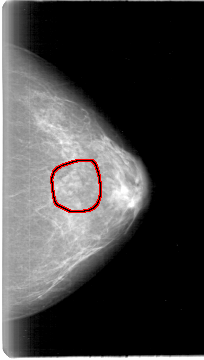

FILE: D_4024_1.LEFT_CC.OVERLAY

TOTAL_ABNORMALITIES 1

ABNORMALITY 1

LESION_TYPE MASS SHAPE LOBULATED MARGINS CIRCUMSCRIBED

ASSESSMENT 0

SUBTLETY 3

PATHOLOGY BENIGN

TOTAL_OUTLINES 1

BOUNDARY